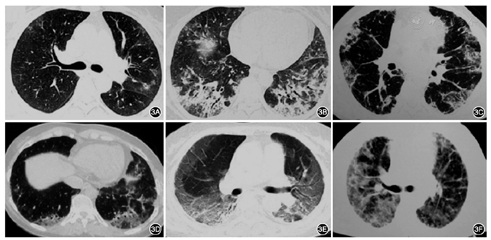

(1)病变性质:以磨玻璃影(GGO)最常见(图1A、图1B、图1D、图1F、图1G),其次为实变影(图1B、图1E、图1H、图1I),也可见结节影(图1A、图1H)、网格索条影(图1C、图1F、图1G)、铺路石征(图1F)、晕征、反晕征(图1I)及马赛克灌注。(2)病变数量:少数轻症患者为单发病灶,多数为双肺多发病灶或者双肺弥漫病变。(3)病变分布:不按叶段分布,沿支气管血管束分布(图1A、图1D)或者沿胸膜下分布(图1B、图1G)。(4)时相特征:病变性质随时间而改变。早期可以为多发片状GGO或者结节(图1A、图1D),病程进展后,GGO病变范围扩大伴有实变影(图1E),可出现索条影和网格影。病程后期可能表现为索条影、胸膜下线(图1C)。部分危重症患者则表现为双肺弥漫实变影和磨玻璃影,即"白肺"。